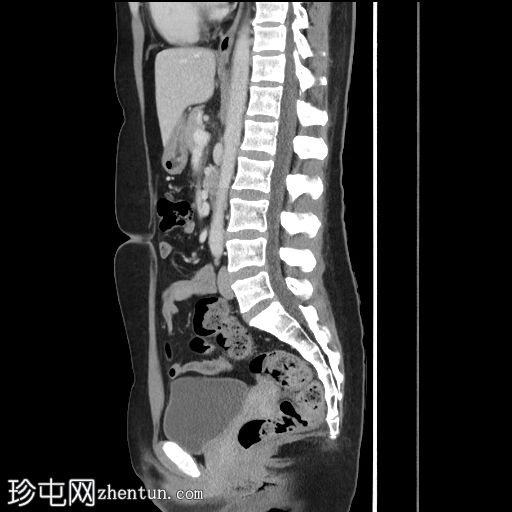

矢状面

9.jpg

非造影

矢状面C+期

在轴向、冠状面和矢状面上均可见肝5/6段病变。动脉期可见周围结节状强化,门静脉期可见进行性向心性充盈,延迟期亦持续存在。这些表现为肝血管瘤的特征性表现。

然而,目前的CT扫描显示动脉期呈周围结节性强化,门静脉期呈进行性向心性充盈,且延迟成像后仍持续存在。这些特征是肝血管瘤的特征。未发现其他肝脏病变。